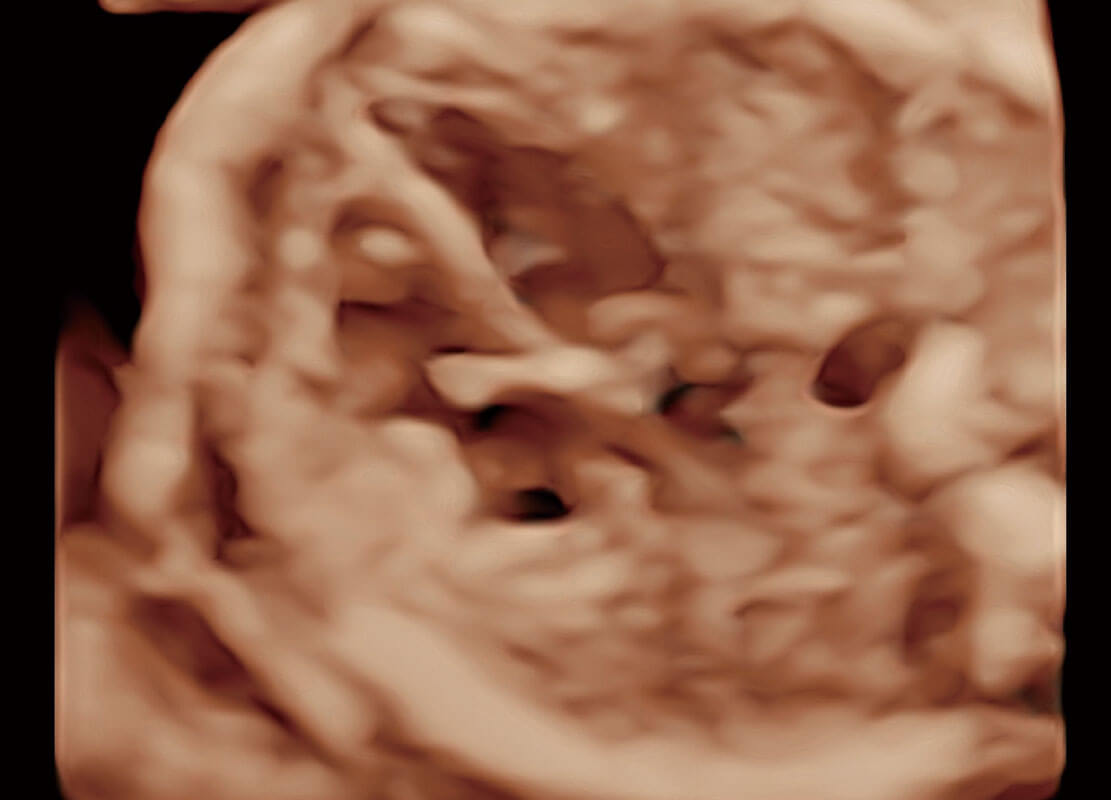

早孕筛查

P60在胎儿早孕期超声筛查中为您带来优异的图像质量。

• 高分辨率容积成像-早孕胎儿